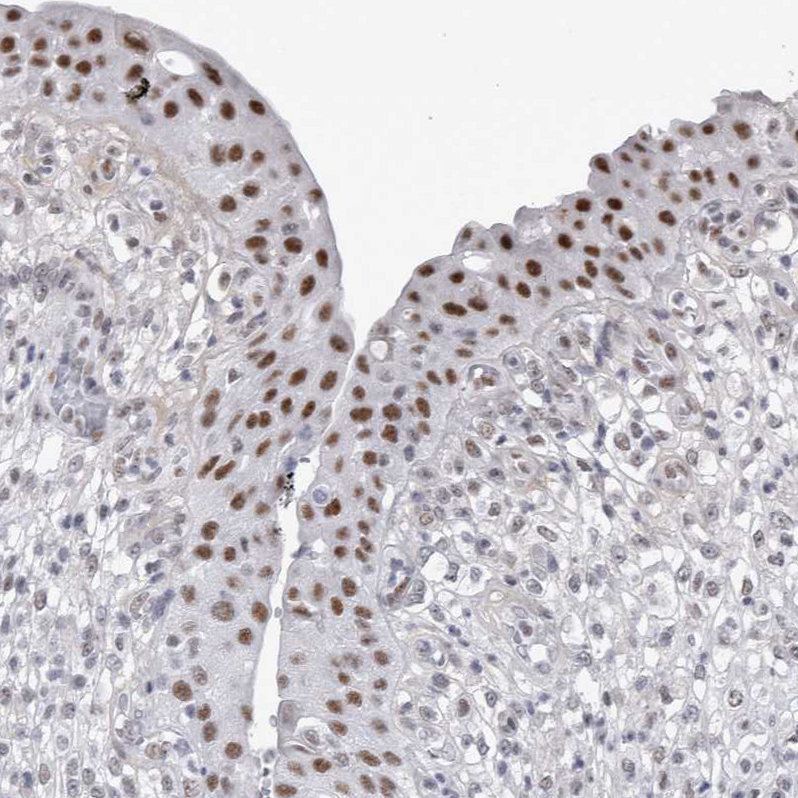

Immunohistochemical staining of human urinary bladder shows strong nuclear positivity in urothelial cells.